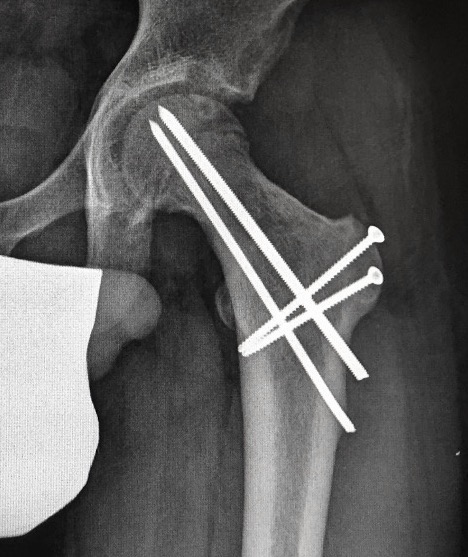

Subtrochanteric fracture

Subtrochanteric fracture likely causes by multiple drill holes / attempts

Cause

Too low screw entry

Multiple drill holes to get correct entry

Management

Intramedullary nail